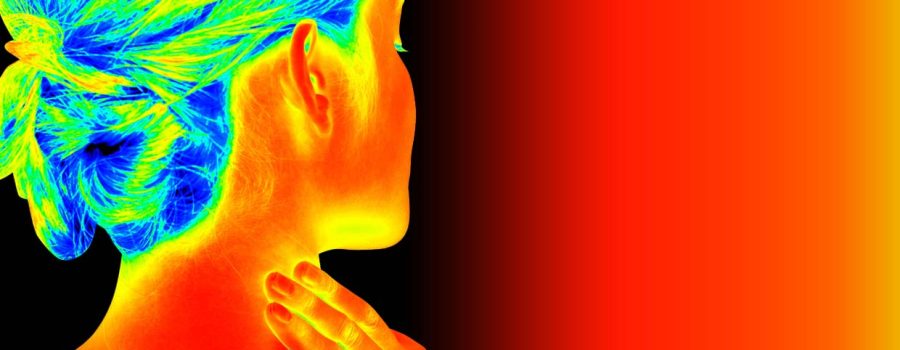

Medical Thermography is a cutting-edge tool in the world of medical imaging. It offers a non-invasive way to assess health. This technique uses thermal imaging to detect heat patterns in the body.

Medical Thermography is a revolutionary diagnostic tool. It employs infrared technology to visualize heat patterns on the skin’s surface. These patterns can indicate underlying health issues.

The technology is similar to that found in thermal cameras. It captures images that show variations in temperature. Warmer areas may indicate inflammation or increased blood flow.

The foundation of thermal imaging lies in physics. All objects emit infrared radiation, which varies with temperature. This radiation is invisible to the naked eye.

Thermal imaging cameras convert this infrared data into clear images. They create visual representations of temperature differences. These images help to detect changes in the body’s heat patterns.

The process starts with the camera detecting infrared radiation. The camera’s sensors translate this data into an electronic signal. This signal forms a vivid thermographic image.

Medical Thermography uses these images for diagnostic purposes. The varying shades represent temperature variations. Hotter areas could indicate inflammation or excessive blood flow.

Medical Thermography relies on sophisticated technology to map heat patterns. These patterns reveal insights into the body’s internal state. By detecting minute temperature changes, it aids in diagnosis.

The process begins with the patient standing or sitting in a controlled environment. This setting minimizes external temperature influences. A thermal camera captures infrared energy emitted from the body.

These cameras convert infrared radiation into temperature readings. This data translates into thermographic images. These images display variations in temperature with different colors.

Red or orange shades often indicate warmer areas. This could suggest inflammation, increased blood flow, or potential issues. Cooler areas appear in blue or green, hinting at reduced circulation or nerve issues.